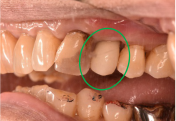

右上(第2小臼歯)の臭いが気になる。

レントゲンで詳しく診てみると、歯根が真っ二つに割れていることがわかりました。臭いは、割れているために炎症を引き起こし、そこからの膿が原因でした。保存することができず抜歯しました。抜歯後、インプラントを埋入しました。

所感

抜歯後、ブリッジ、部分入れ歯の選択肢もありましたが、2013年に右下にインプラント治療をし、インプラントの良さを十分に理解しておられましたので、今回も1本歯を失ったところにインプラント治療を希望されました。歯根破折が原因で抜歯になった方ですので、もしブリッジにしていたら再度歯根の破折を引き起こし、さらに歯を失う可能性が、高い方でした。インプラントは、それ自身が単体で植立し、単独で咬合力を負担します。ブリッジや部分入れ歯のように他の歯に歯がない部分の負担を負わせることがないので、他の歯を守ります。インプラントにして正解だと考えます。今回もX-Guideを使った埋入で、安心安全に行うことができました。

Before

歯根が真っ二つに割れていました

抜いた歯

【抜歯後】

After